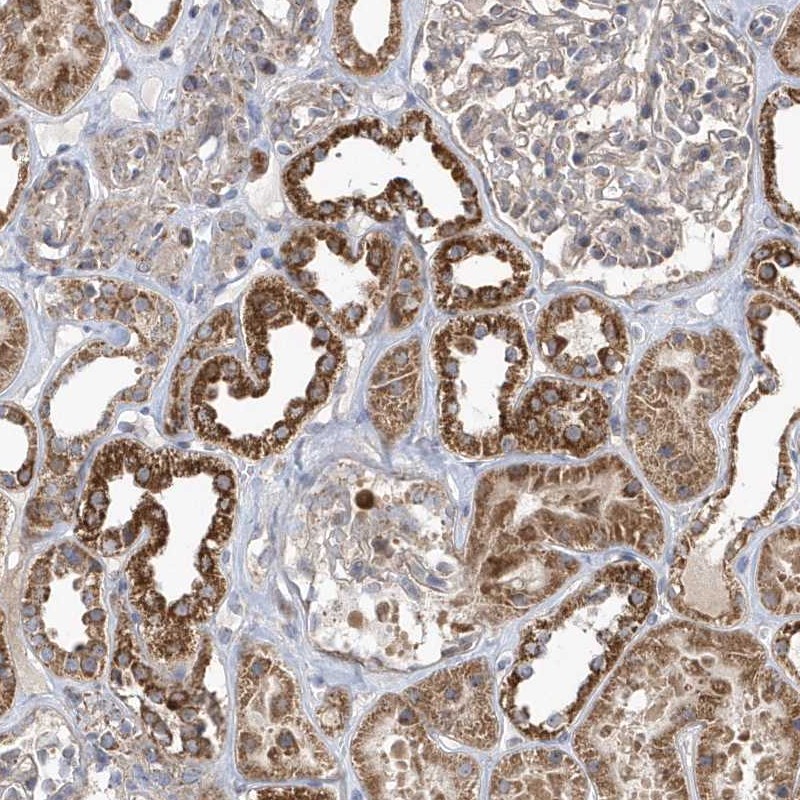

Immunohistochemical staining of human kidney shows strong cytoplasmic positivity in cells in tubules.